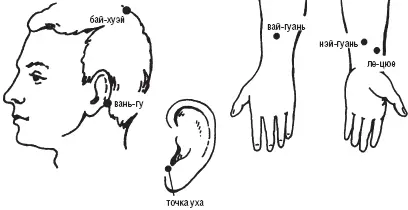

Владимир Васичкин - Лечебные точки организма - снимаем боли в сердце и в области живота

- Название:Лечебные точки организма: снимаем боли в сердце и в области живота

Лечебные точки организма: снимаем боли в сердце и в области живота: краткое содержание, описание и аннотация